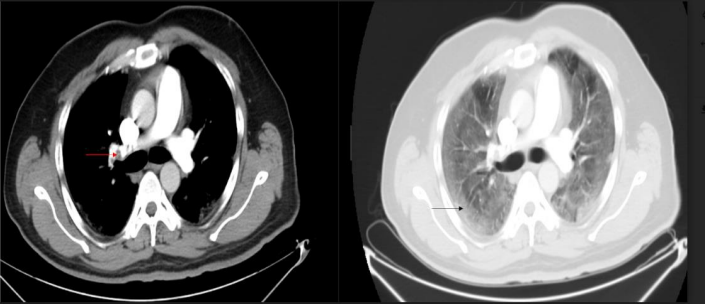

A 44-years old man presented with dyspnea for 4 days and was admitted

into the hospital with low oxygen levels. At the time of admission, his heart rate was 112 beats/minute, and oxygen saturation levels were low at 83% on room air. Laboratory tests showed elevated WBC count, high levels of BNP, troponin, CRP, lactate dehydrogenase, D-dimer, ferritin and procalcitonin. RTPCR from nasopharyngeal swab was positive for COVID-19. D-Dimer was elevated. CTPA demonstrated filling defect at bifurcation of right pulmonary artery and extends into its right descending branches indicating pulmonary thrombosis (Figure 3).

Figure 3: Axial CTPA demonstrated filling defect at bifurcation of right pulmonary artery and extending into its right descending branches indicating pulmonary thrombosis (red arrow). GGOs were seen in all lobes of both lungs in axial lung window (black arrow).

GGOs were seen in all lobes of both lungs (Figure.3). The patient underwent a successful mechanical thrombectomy using FlowTriever, which improved his oxygenation. Nasopharyngeal PCR test returned positive for COVID-19. He was administered antibiotics, hydroxychloroquine, and anticoagulation. Despite these treatments, his condition deteriorated with worsening lung inflammation. The patient finally succumbed to COVID-19 infection and pulmonary thromboembolism.